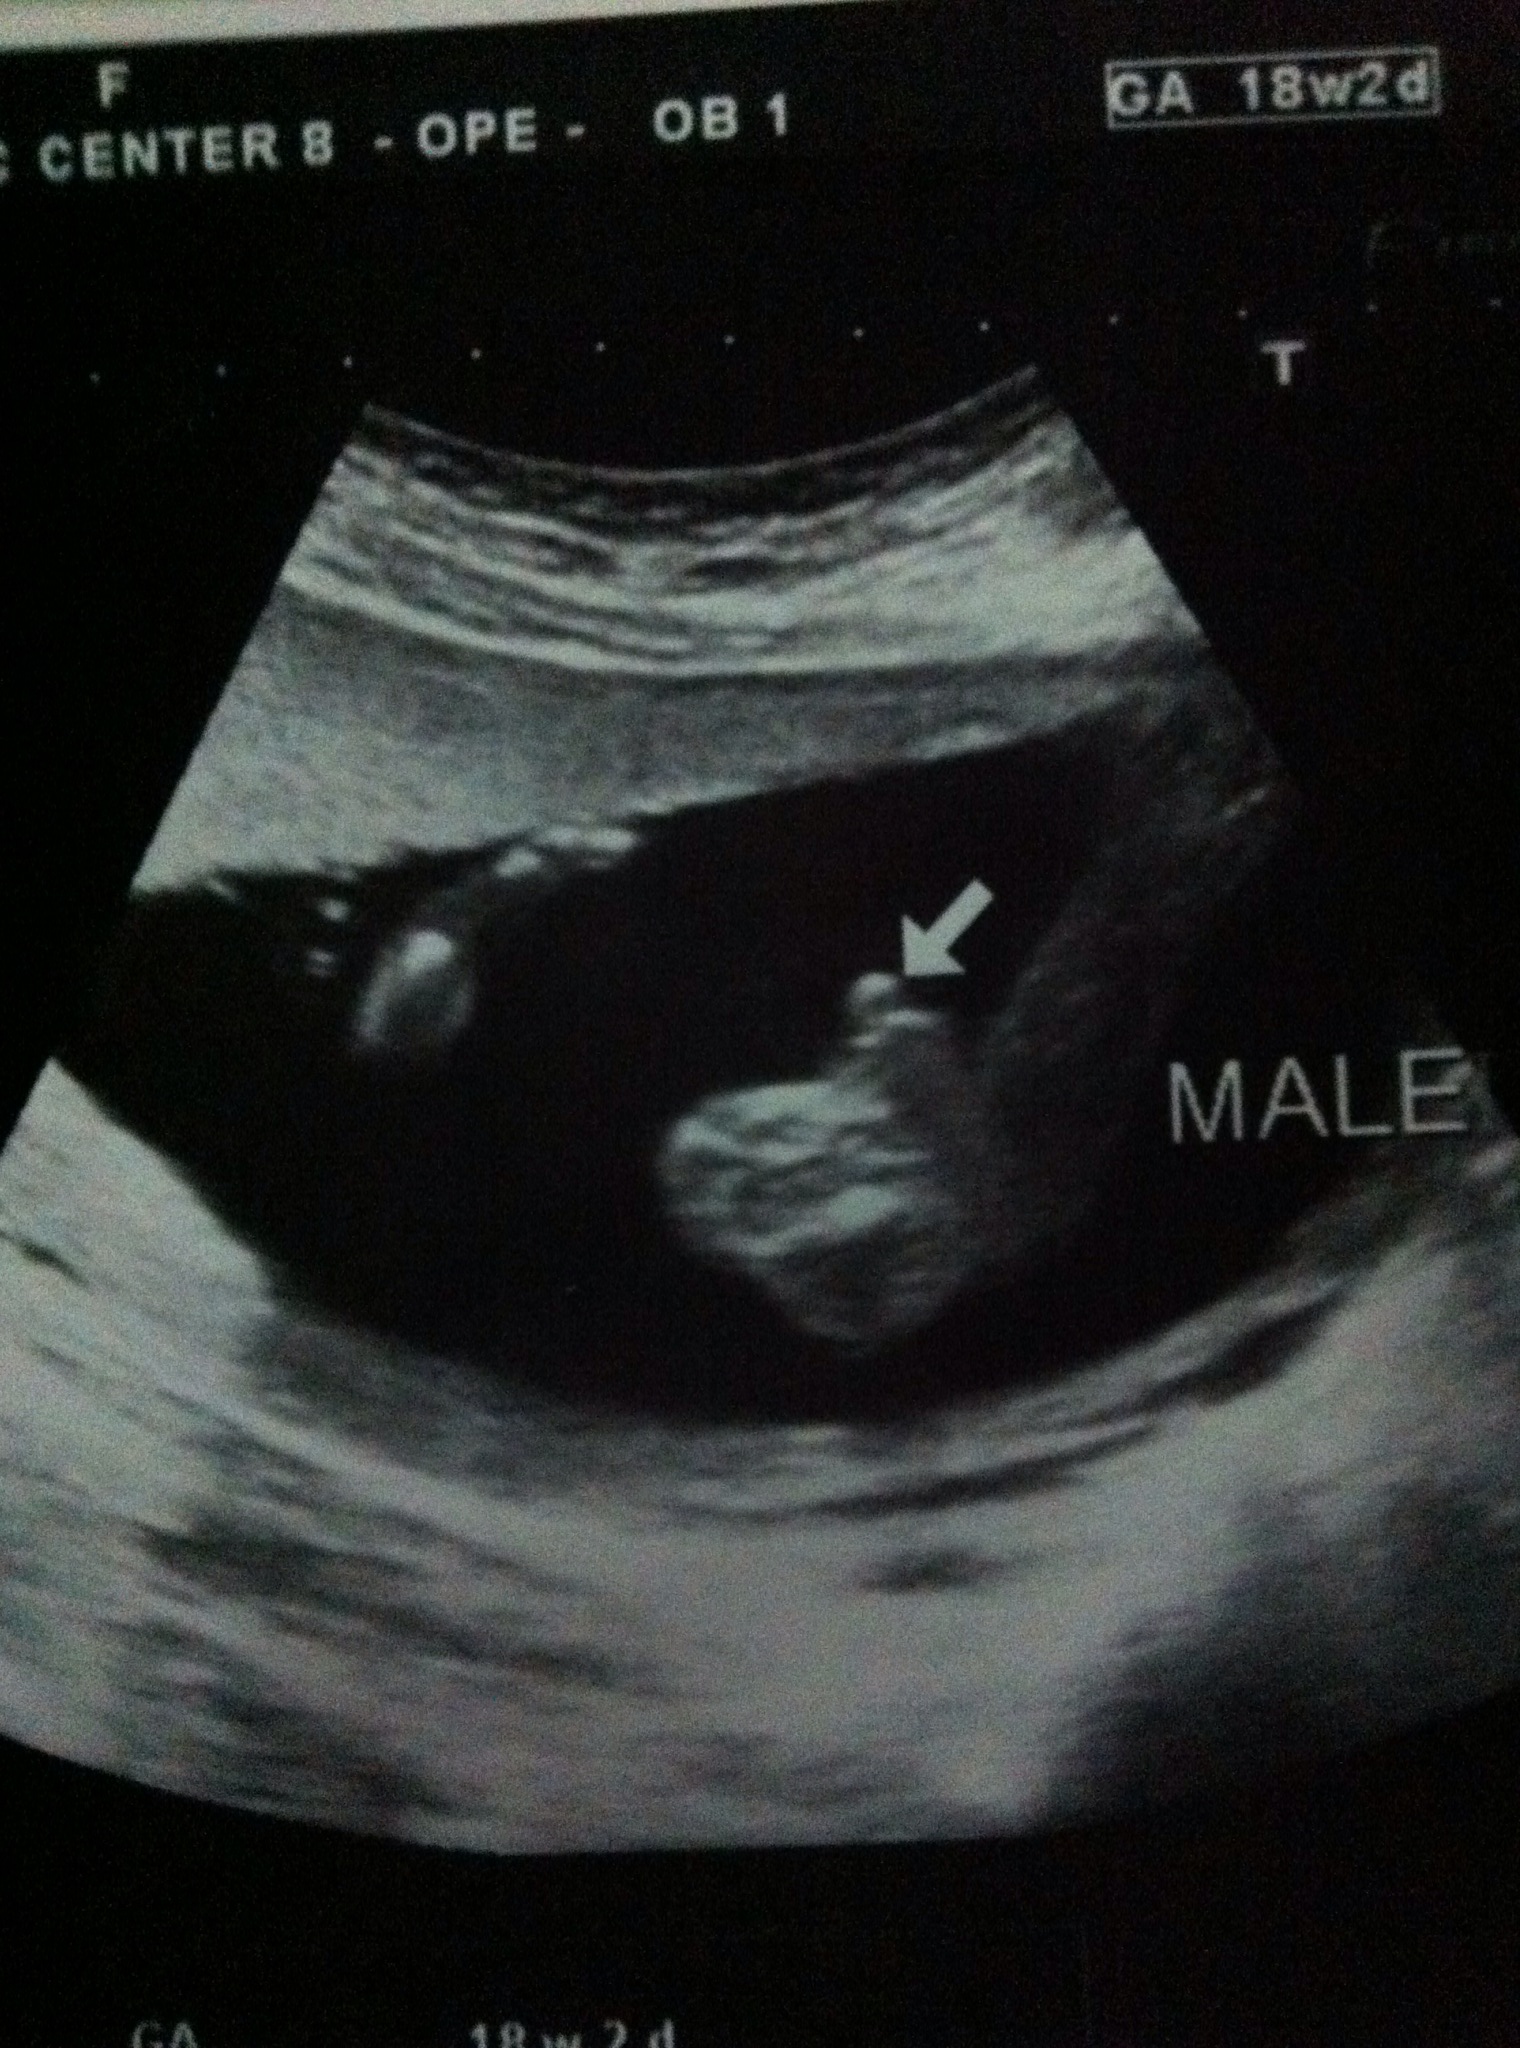

อยากให้เพื่อนๆโชว์รูปอัลตราซาวด์ของเจ้าตัวเล็กค่ะ

อันนี้ ของเจ้าของกระทู้นะคะ หมอบอกว่าเป็นผู้ชายค่ะ (แต่แอบกลัวจะพลิกเป็นผู้หญิง555 ดูไม่ค่อยออก)